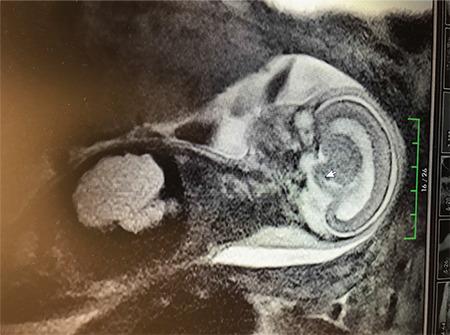

What is your diagnosis?